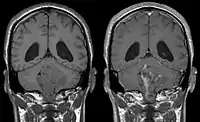

Ependymoma of 4.ventricle in MRI.

Ependymoma of 4.ventricle in MRI. Left without, right with contrast-enhancement.